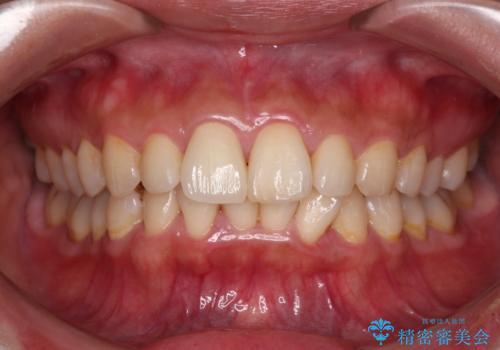

転んで欠けてしまった前歯 オーダーメイドのオールセラミッククラウン

- 転んで欠けてしまった前歯を気にして来院された患者様です。

転んだ際に歯の先端1/4ほどが欠けてしまい、近医にて修復をしてもらったとのことですが、将来的にオールセラミッククラウンを装着する可能性を説明されたため、当院にて補綴治療を行うこととしました。

オーダーメイドタイプのセラミッククラウンは、既製タイプのク色のラウン(スタンダードタイプ)とは異なり、色合いが合うまで何度も修正を行って調整をいたします。